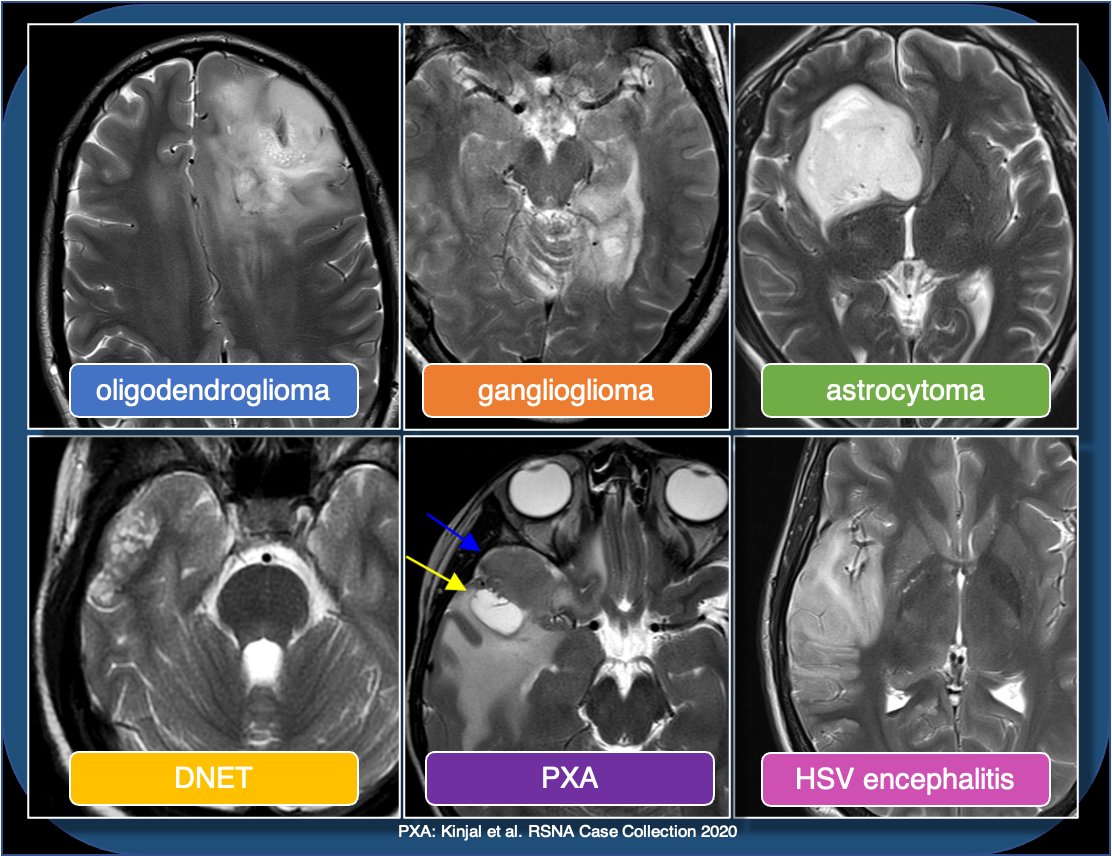

Ddx for cortically based tumors in child/young adult includes oligodendroglioma (usually middle-aged adults, often with Ca++), DNET (bubbly, uncommon enhancement), PXA (prominent nodular enhancement), and astrocytoma (usually low grade). Encephalitis can also look similar.

This is less likely to be a glioblastoma, which is usually centered in supratentorial WM, with thick peripheral enhancement, and centrally necrotic.